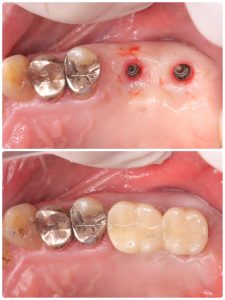

インプラントセット

ペリフィケーションインデックスでの印象

スキャンボディは複数本の場合は正確では無い為使わない コツだね

デンサーリフトで3ヶ月でセット💪